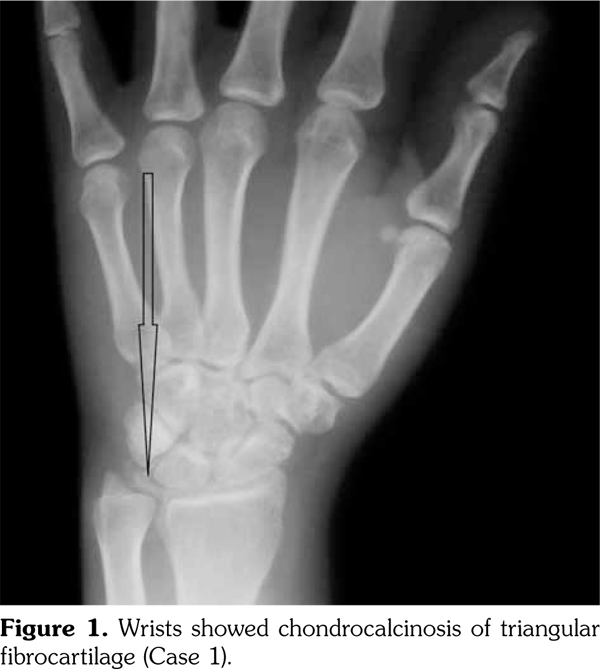

On examination, there was swelling and painful restriction of movement in her right knee. Imaging revealed calcification of cartilage of wrists, knee joints and hip joints although no microscopic confirmation was possible at this stage (Figure 1-4). She was investigated for a possible cause for CC, although investigations to screen for a metabolic cause turned out to be negative with a possibility for hereditary CC.

Case 2- A 39-year-old male patient presented with swelling of both knee joints. He also gave a history of recurrent painful swelling of knee joints and wrist joints for more than 10 years and was treated by an Ayurvedic physician. Other medical history or family history of medical problems were insignificant. There was a massive swelling of both knee joints with effusions, which was aspirated and the X-rays revealed calcification of the articular cartilages (Figure 5). A written informed consent was obtained from the patient.